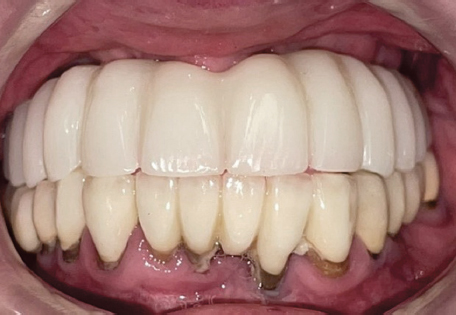

Таким образом постоянная конструкция устанавливается в полости рта (рис. 25, 26).

Рис. 25. Фотографии постоянной конструкции в полости рта

Fig. 25. Photographs of permanent structure in the oral cavity